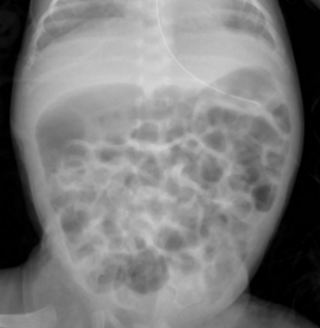

临床病例:患儿日龄1个月12天,女,孕1产1,在孕26周时因“胎盘早剥”剖宫产娩出,无胎膜早破,血性羊水,出生体重660g,双胎之先娩出者,生后Apgar评分1分钟为8分,5分钟、10分钟均为9分,以“超早产儿、超低出生体重儿、新生儿呼吸窘迫综合症、双胎儿”转入我科进一步治疗。患儿入院后予早产儿配方奶喂养。患儿奶量增加缓慢。表现为腹胀、肠鸣音弱、奶量增加困难、偶有吐奶、排粘液便。无肉眼血便。化验检测显示嗜酸性粒细胞增高,波动在20-25%之间。间断监测腹片显示肠管僵直、肠管充气不均匀(如下图所示)。未见肠壁积气和门静脉积气。患儿有过敏性疾病家族史。予更换为深度水解奶后患儿腹胀较前缓解,肠管充气均匀,无明显扩张。奶量增加顺利。嗜酸性粒细胞下降至5-8%。

更好奶粉前